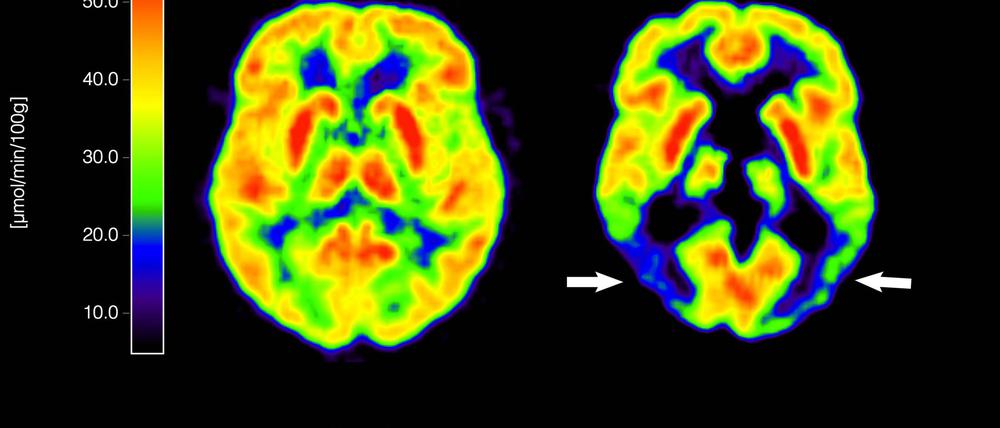

Der Antikörper, der seit Anfang 2023 bereits unter dem Handelsnamen Leqembi in den USA zugelassen ist, soll das Proteinfragment beta-Amyloid (Aß) aus dem Gehirn entfernen. „Amyloid ß steht vermutlich am Beginn einer Kaskade der neuronalen pathologischen Veränderungen im Gehirn“, sagte Jörg Schulz von der Uniklinik Aachen und Sprecher der Kommission „Demenz und Kognitive Störungen“ der Deutschen Gesellschaft für Neurologie (DGN).